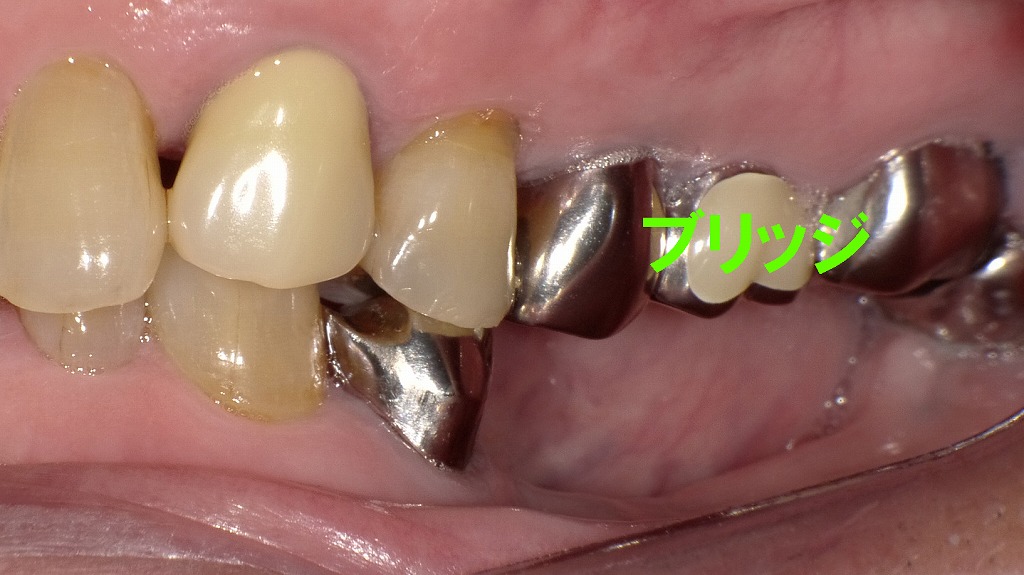

ブリッジの実例から考える最適な治療選択

一見問題なく見えても、ブリッジは支台歯への負担増加や清掃のしにくさ、将来的なむし歯・歯周病のリスクが高まることがあります。

インプラントが「絶対ダメ」と思い込む前に、現在の支台歯の状態や残存歯の負担、長期的な予後を総合的に考えることが大切です。